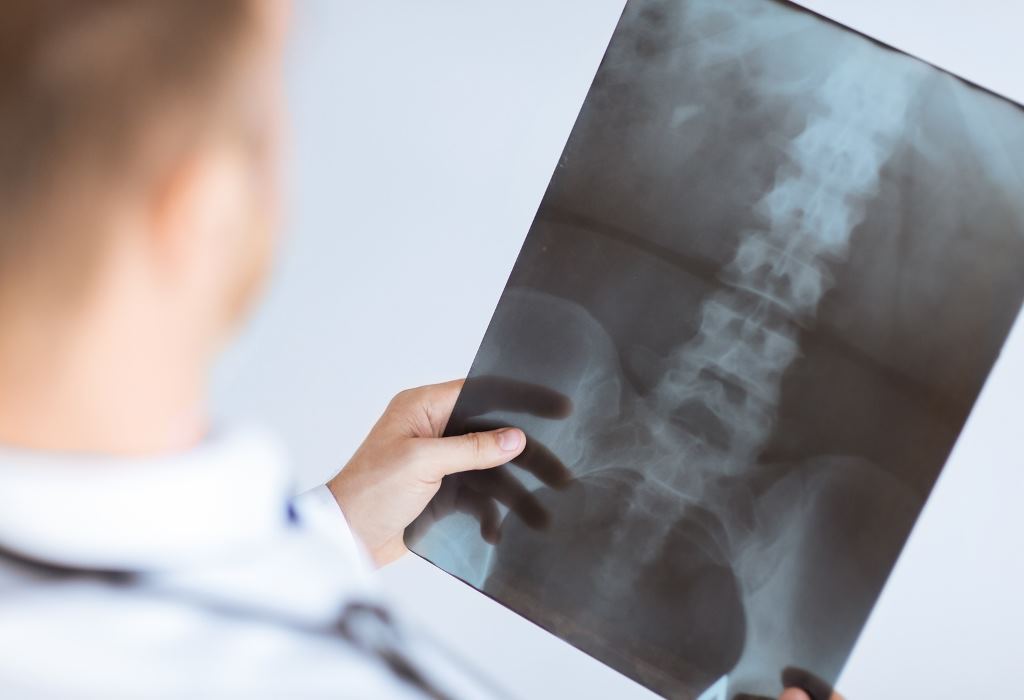

Диагностика

Перед тем как лечить патологию, важно выявить ее, обнаружить первопричину и степень запущенности. Установление диагноза опирается на жалобы больного и осмотр врача, для подтверждения заболевания показаны обследования:

- УЗИ-диагностика для оценки состояния мягких тканей сустава и наличия жидкости.

- Лабораторные исследования: общие клинические анализы крови и мочи, кровь на уровень сахара, гормональный фон, холестерин и биохимию.

- Рентгенография. При выявлении наростов эта диагностическая мера обязательна, т. к. на рентгене можно увидеть точную локализацию, размер костных наростов, вид и степень поражения. Крупные наросты по форме очень похожи на птичьи клювы.

- КТ для исследования мягких тканей.

- МРТ для выявления остеофитов используется редко. Назначают при затрудненном диагностировании заболевания, когда врачу нужно дополнительное подтверждение состояния тканей и костей сустава.

Иногда лечащий врач назначает проведение артроскопии.